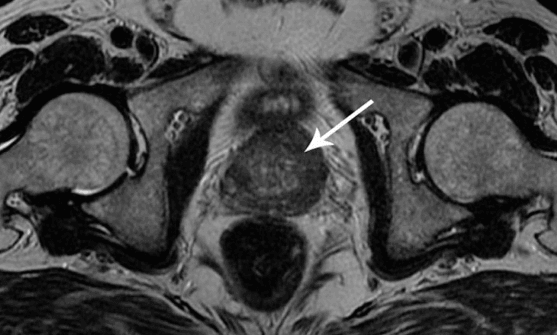

interesting image

Cancer de la prostate chez un homme de 58 ans.